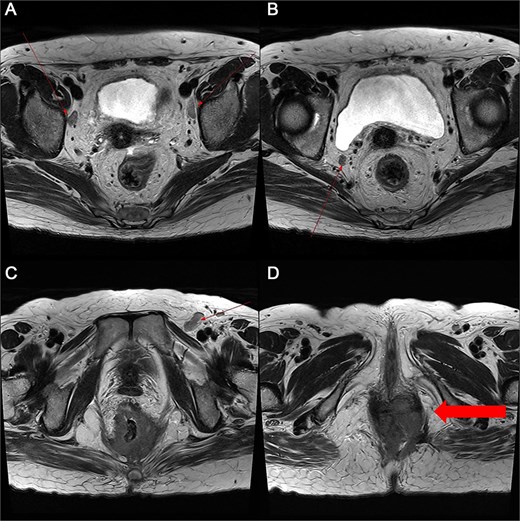

Pelvic MRI demonstrating the progression and extent of perineum and pelvic involvement. (A–C) Indeterminate lymph nodes in the bilateral external iliac chains, right obturator chain, and bilateral inguinal chains (thin arrow). (D) Presence of anorectal cancer with invasion of both levator muscles (thick arrow).